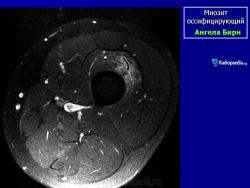

Рентгенологические признаки однотипны для всех форм оссифицирующего миозита; плотный рисунок периферической и менее плотный центральной части повреждения.

При компьютерной томографии визуализируется кальцификация гетеротопической кости, которая продвигается от наружного края образующегося узла в центр.

Рентгенологические признаки однотипны для всех форм оссифицирующего миозита; плотный рисунок периферической и менее плотный центральной части повреждения.